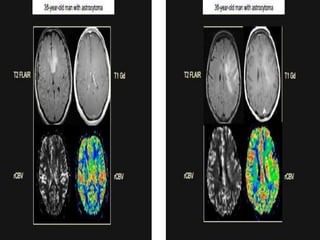

Forty-nine-year-old woman with a glioblastoma in the frontal lobes. The

region within the tumour with pronounced signal enhancement is marked

with circle on ASL CBF, DSC rCBF (colour-coded) and DSC rCBV (grey scale).